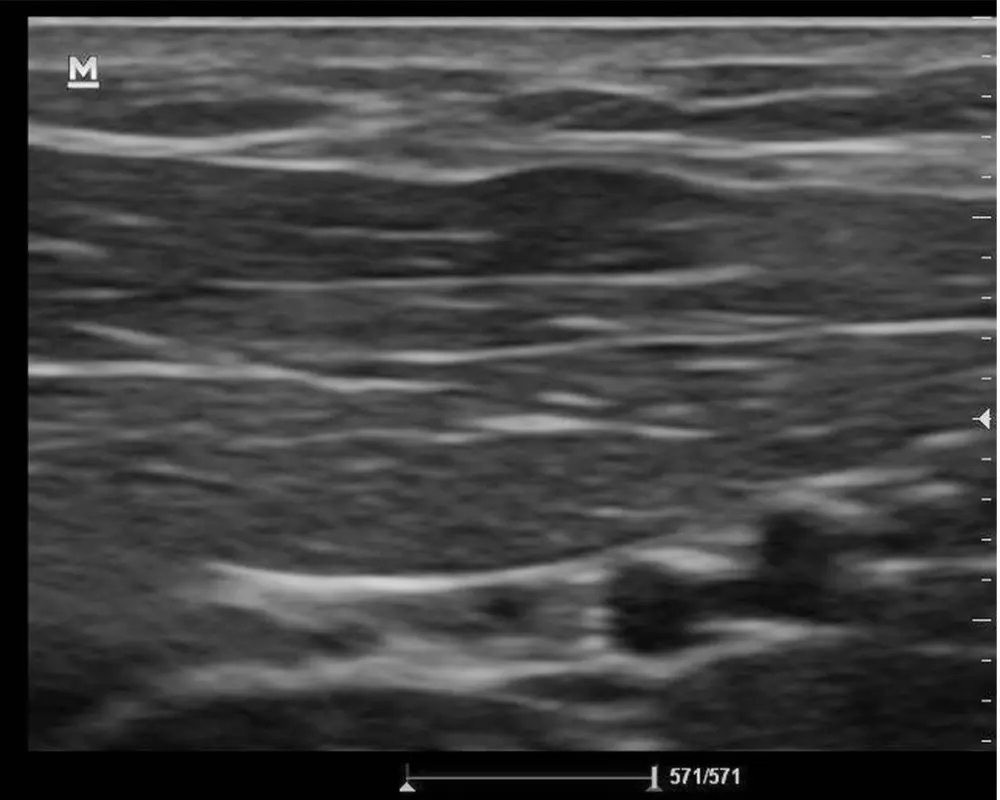

Thyroid Ultrasound

This ultrasound scan examines the thyroid gland to detect nodules, swelling, or abnormalities, helping providers evaluate function and determine the need for further medical care.